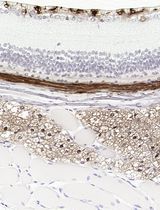

采用 Davidson 固定液和黑色素漂白法优化小鼠眼组织切片的免疫组化染色

Anne Nathalie Longakit [...] Catherine D. Van Raamsdonk

2025年11月20日 1547 阅读